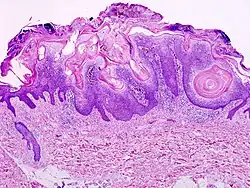

Seborrheic keratosis close-up

Visual diagnosis is made by the "stuck on" appearance, horny pearls or cysts embedded in the structure. Darkly pigmented lesions can be challenging to distinguish from nodular melanomas.[10] Furthermore, thin seborrheic keratoses on facial skin can be very difficult to differentiate from lentigo maligna even with dermatoscopy. Clinically, epidermal nevi are similar to seborrheic keratoses in appearance. Epidermal nevi are usually present at or near birth. Condylomas and warts can clinically resemble seborrheic keratoses, and dermatoscopy can be helpful to differentiate them. On the penis and genital skin, condylomas and seborrheic keratoses can be difficult to differentiate, even on biopsy.

A study examining over 4,000 biopsied skin lesions identified clinically as seborrheic keratoses showed 3.1% were malignancies. Two-thirds of those were squamous cell carcinoma.[11] To date, the gold standard in the diagnosis of seborrheic keratosis is represented by the histolopathologic analysis of a skin biopsy.[12]